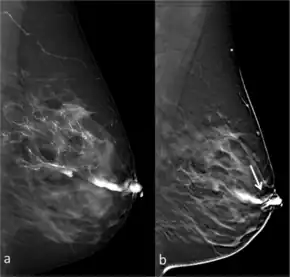

![]() Full-field digital (FFD)-galactography (left) and Digital breast tomosynthesis (DBT)-galactography (right) showing intraductal papilloma. | |